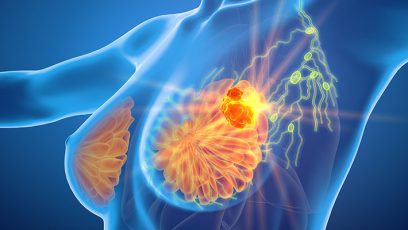

SABCS 2023

Oncology / Hematology • No. 15 • 2023